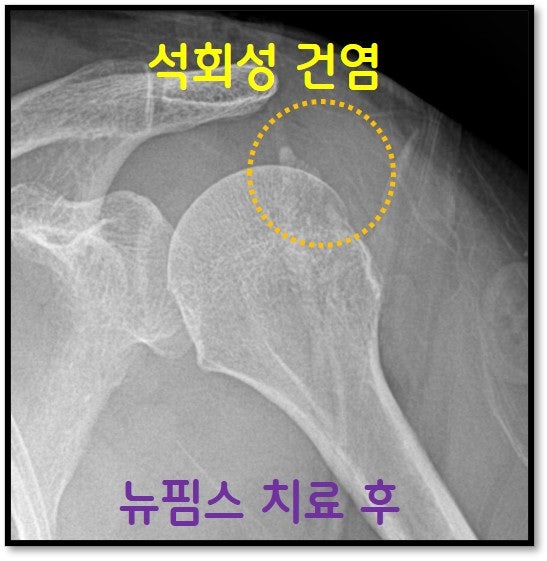

상기 영상과 같이 치료를 진행한 후 X-ray 를 보겠습니다.

약간의 석회가 남아있지만 환자분의 통증은 거의 없어 졌습니다. 약간의 석회는 스스로도 흡수가 진행되겠지만 차 후 체외충격파 치료를 통해 추가적 치료를 하면 거의 다 석회가 없어질 것으로 생각됩니다. 어깨 석회성 건염은 수술없이 치료 될 수 있습니다. 석회의 양상에 따라 석회분쇄흡입술 하는 방법에 차이가 있습니다. 어떠한 석회는 분필처럼 딱딱한 경우(형성기, 유지기)도 있고 치약처럼 찐득찐득한 경우(흡수기) 도 있습니다. 석회의 성질이 다르기 때문에 석회분쇄하는 방법도 다릅니다. 이를 구분하고 모든 경우에 다 성공적으로 할 수 있는 경험 많은 의사 선생님께 치료 받는다면 석회성 건염은 더 이상 '수술이 필요없는', '두려울 것이 없는 질환'이 될 거라 생각합니다. 석회성 건염으로 고생하시는 환자분들께 뉴핌스치료(석회분쇄흡입술)는 분명 수술없이 치료 될 수 있는 획기적인 치료법이 될 거라 생각합니다.